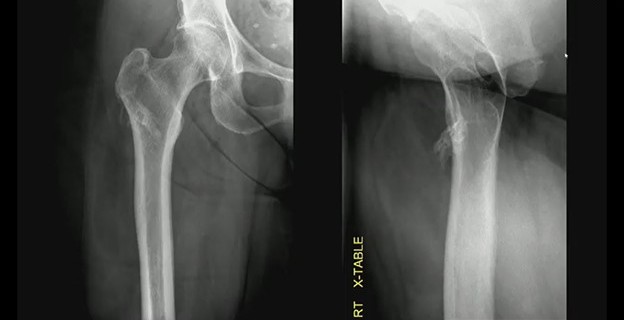

Imaging: Two views of an unusual surface lesion coming from the femur. Bone exostosis is evident. On the right, it doesn’t appear there’s any communication with the marrow space. Looking at soft tissues, you can make out a large, low-density mass—sort of draped below that little piece of bone coming off of the cortex.

CT shows the bone exostosis corresponds with this lesion coming from the surface of the cortex. It does *not* involve the medullary space; it doesn’t extend through the cortex. That low-density mass corresponds with this very fatty mass atop the bone.